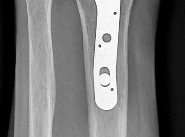

Question 3:

A 55-year-old male undergoes excision of a large cartilaginous tumor of the proximal femur. Molecular analysis of the tumor reveals a mutation in the isocitrate dehydrogenase 1 (IDH1) gene. This mutation is a hallmark of and most frequently associated with which of the following conditions?

Correct Answer: Ollier disease

Explanation:

Mutations in the IDH1 and IDH2 genes are heavily implicated in the pathogenesis of cartilaginous tumors. Somatic mosaic mutations in these genes are found in over 80% of patients with Ollier disease and Maffucci syndrome, both of which are forms of enchondromatosis. Multiple Hereditary Exostoses is associated with EXT1/EXT2 mutations. McCune-Albright is associated with GNAS mutations. NF1 is associated with the neurofibromin gene.